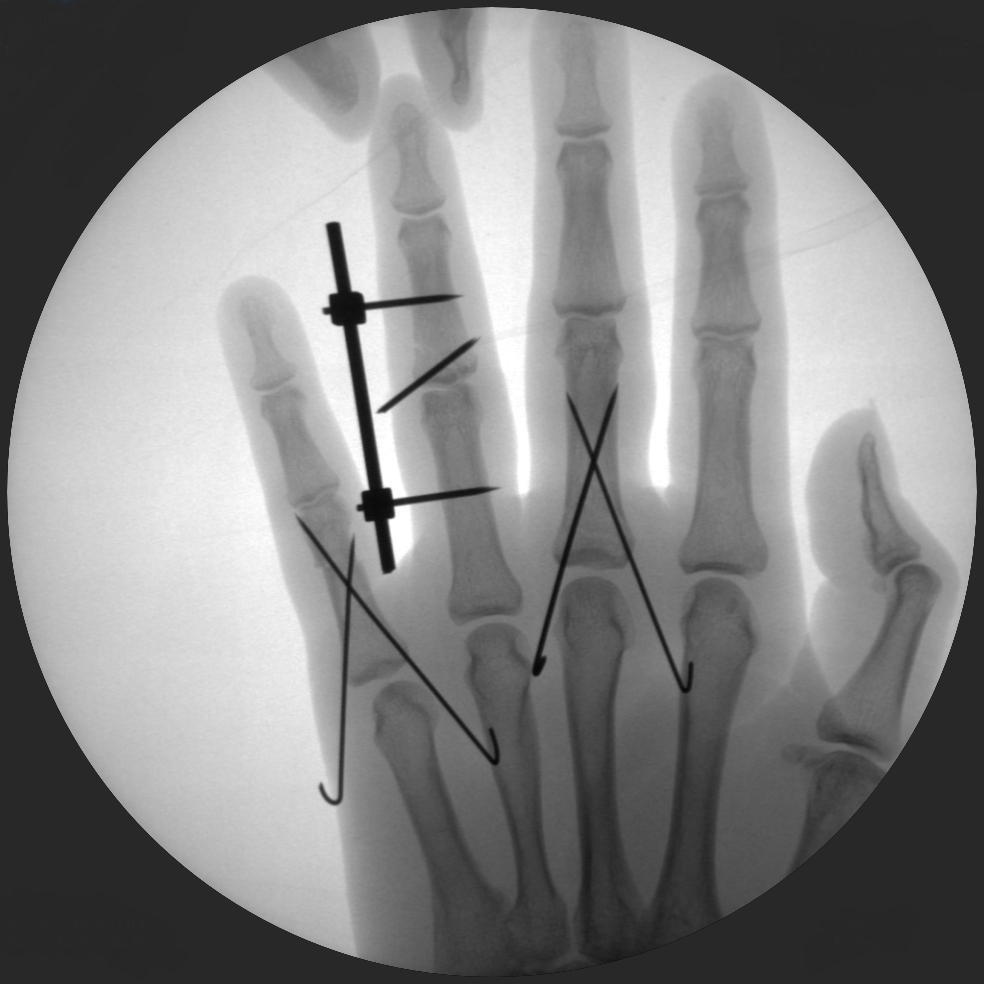

CRIF - Closed reduction internal fixation

ORIF - Open reduction internal fixation